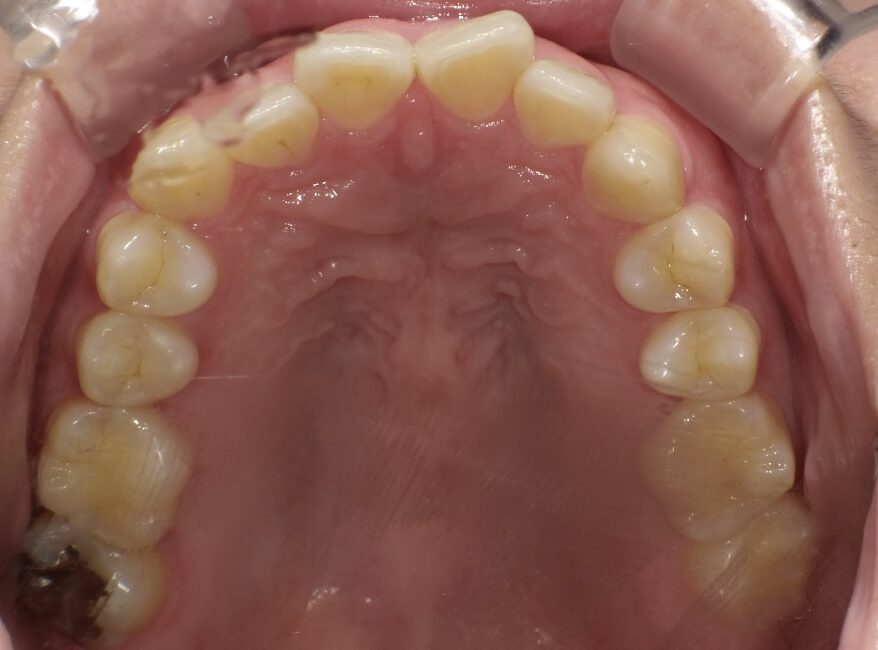

過蓋咬合

ガタガタを主訴に当院を受診され、上下前歯部に叢生(ガタガタ)と過蓋咬合(上の歯が下の歯を深く覆いかぶさっている状態)を認めました。

IPRを使用してマウスピース型矯正装置(インビザライン)を使用し過蓋咬合及び叢生の改善を行いました。

年齢/性別30代女性

抜歯部位非抜歯

治療期間1年6ヶ月